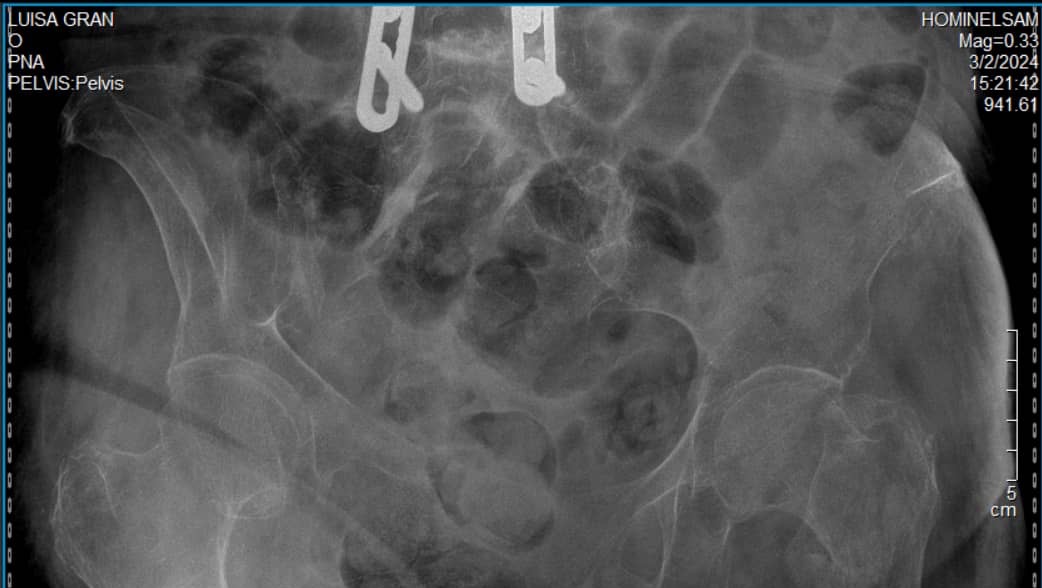

Estoy buscando apoyo económico para poder ayudar a mi madre quien en estos momentos está necesitando ser operada por una caída que sufrió el día sábado 3 . Esta caída le ocasionó una fractura en el cuello del fémur izquierdo con desplazamiento y debe ser intervenida para colocarle un tornillo y poder darle movilidad y evitar quede postrada en una cama que es lo que más se está evitando con ésta operación.